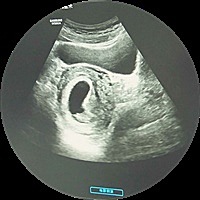

孕36周+3天